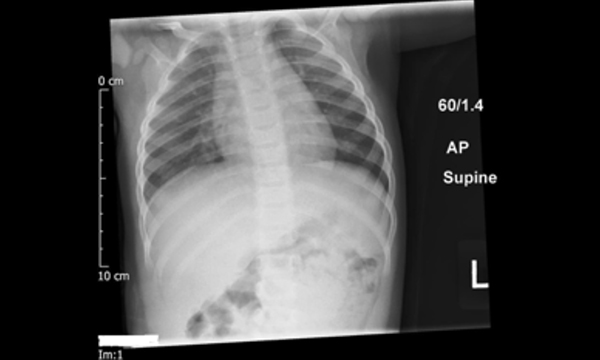

Indications for chest X-rays in children and how to obtain and interpret them

Chest X-ray (CXR) is one of the most common radiological investigations undertaken in practice with children. CXRs are requested for a number of suspected diagnoses, including pneumonia, pneumothorax and foreign body aspiration or ingestion. They may also be requested as part of a skeletal survey or to confirm the position of central and umbilical lines, as well as nasogastric tubes.